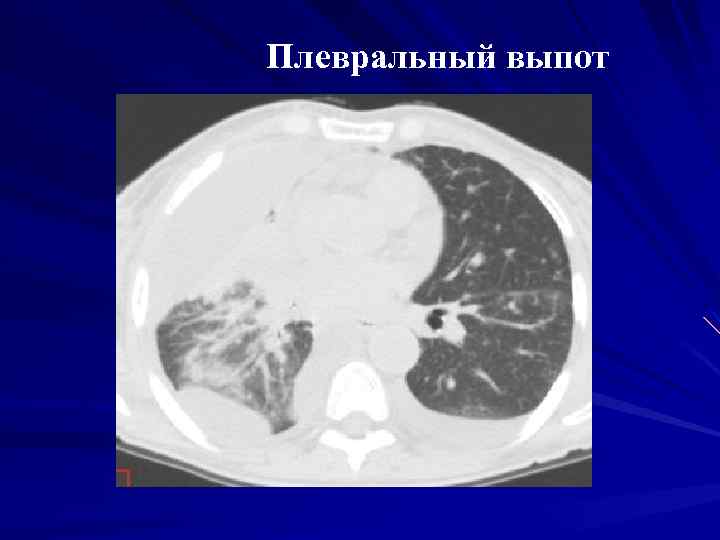

Диагностика плеврального выпота: что нужно знать